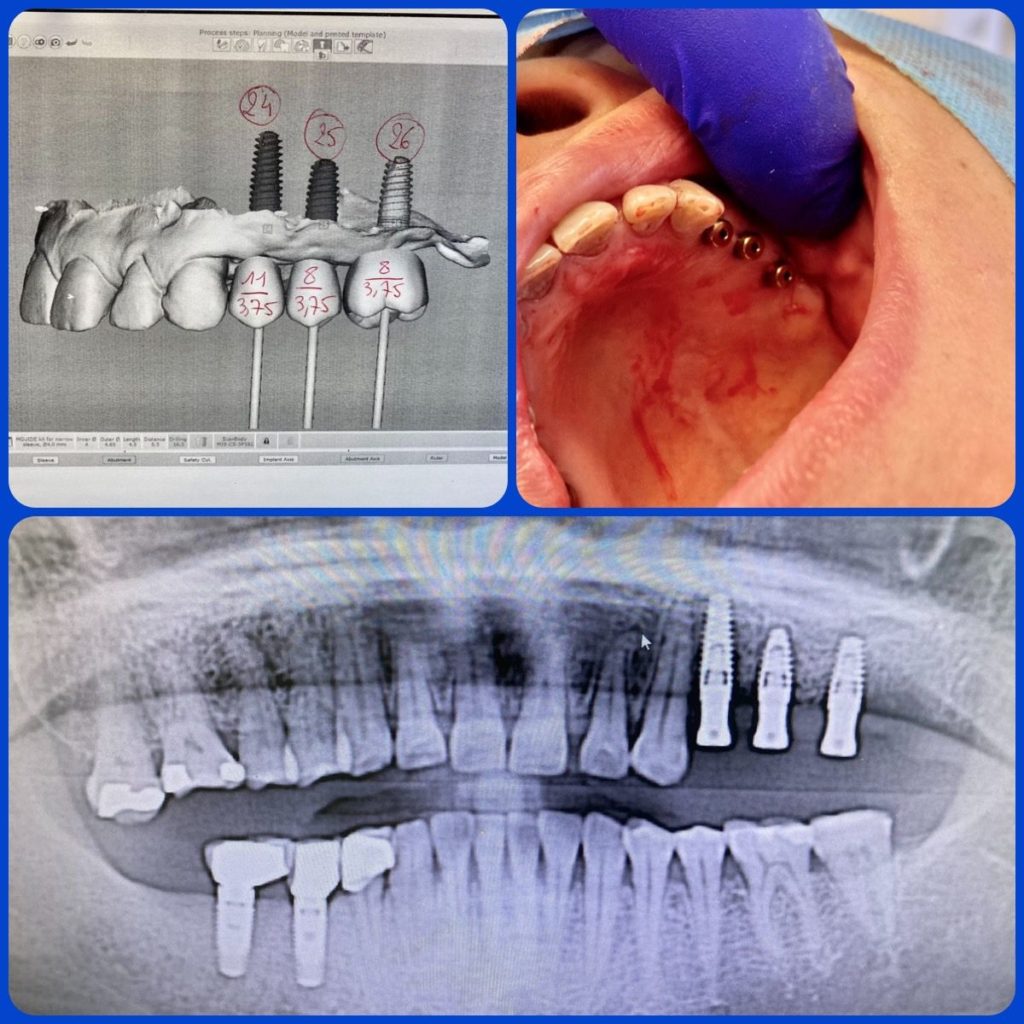

Quels sont les implants dentaires ?

Les implants dentaires sont destinés à compenser les racines des dents. Les implants représentent une base saine et solide pour les dents de rechange fixes (permanentes) ou amovibles qui sont faites pour être identiques à vos dents naturelles.